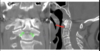

Jefferson fracture (radiogrph and CT)

atlas

What was replaced in the CT shown?

The codyles were replaced in the axis after cervical dislocation